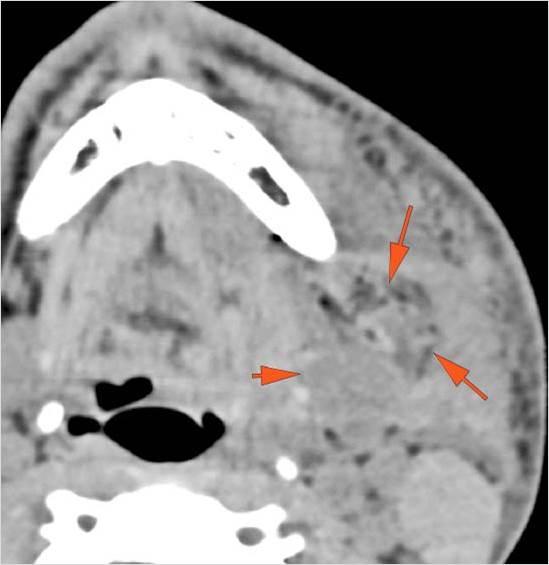

There is localized edema, hematoma or abscess within in the facial or scalp soft tissues, SMAS, infratemporal fossa, masticator space or oral cavity.

There is evidence of gas or a foreign body at a possible fracture site, indicative of an open or penetrating injury.

There is soft tissue swelling suggesting injury to the parotid or submandibular glands.